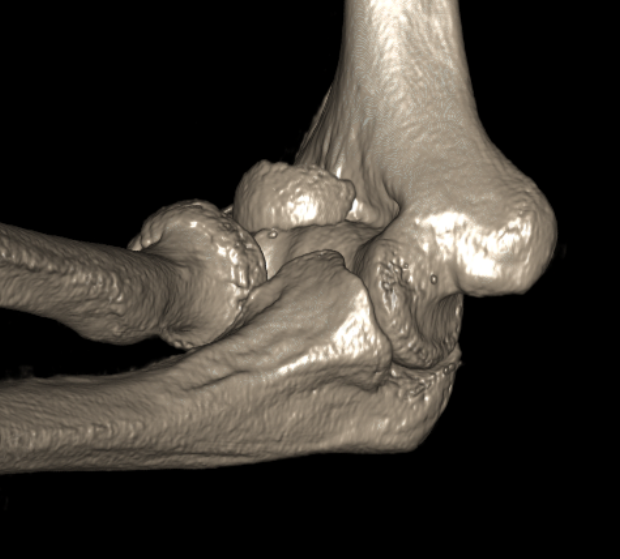

Dubberly Classification

Type I Type Ii Type III

Capitellar fracture

Capitellum + trochlea fracture

In one piece

Capitellum + trochlea fractures

In two separate pieces

Concomitant injuries

Radial head

Watts et al JBJS Br 2007

- 79 capitellar fractures

- 24% had a radial head fracture as well

LCL

Dubberley et al JBJS Am 2006

- 27 capitellum fractures treated with surgery

- 41% had associated LCL injuries

- 7/11 LCL injuries were avulsion fractures of the lateral epicondyle

Capitellum fracture with radial head fracture

Capitellum fracture with radial head dislocation due to LCL injury